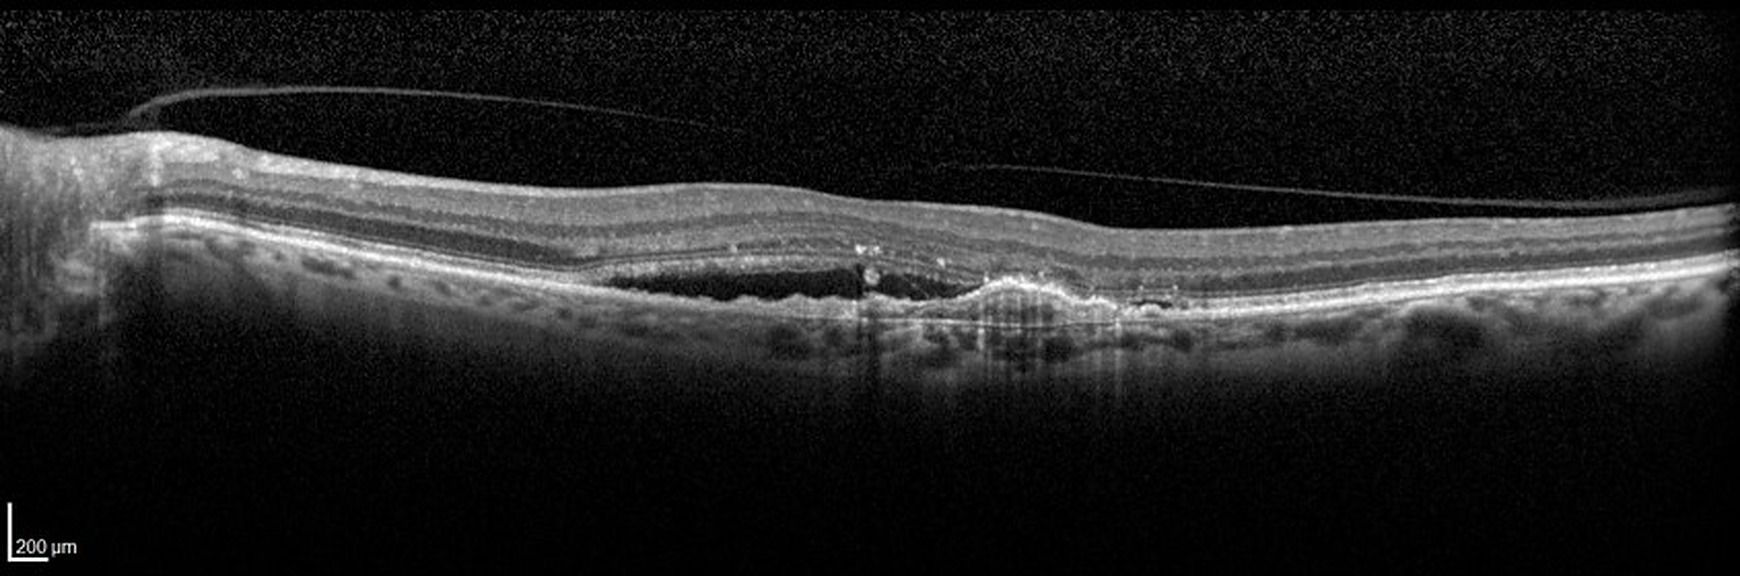

La dégénérescence maculaire liée à l'âge DMLA est la première cause de malvoyance après 50 ans dans les pays développés. Il est donc essentiel de pouvoir l'identifier sous toutes ses formes afin de la prendre en charge quand la pathologie présente des traitements.

Rappeler les différentes formes cliniques et leurs évolutions

Identifier les signes cliniques de chaque type de DMLA

Savoir les diagnostiquer en s'appuyant sur les examens complémentaires